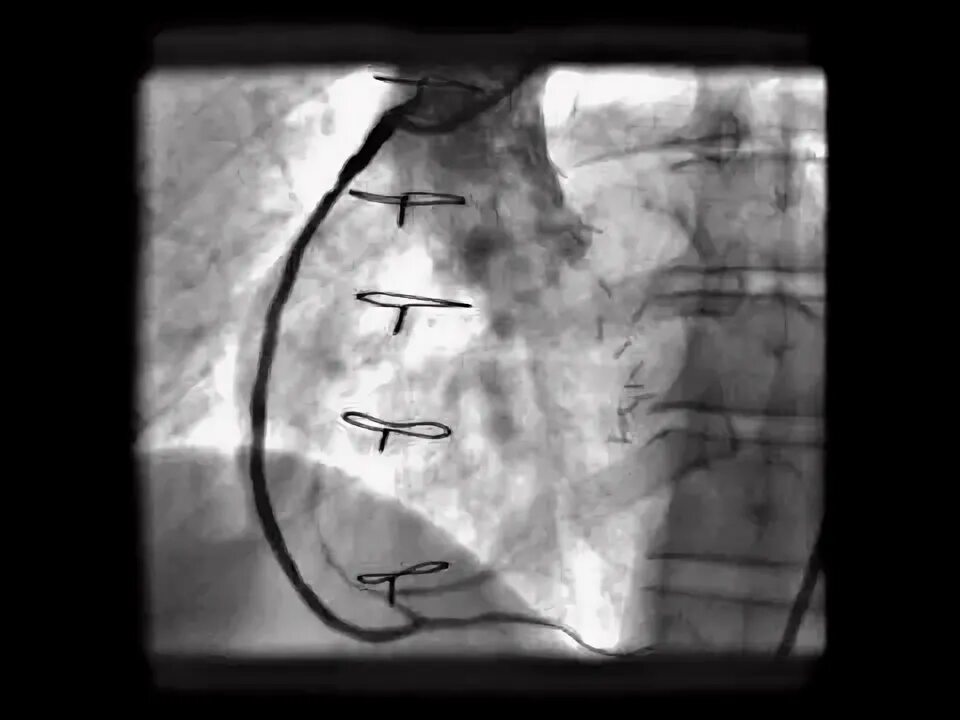

Стентирование срок больничного